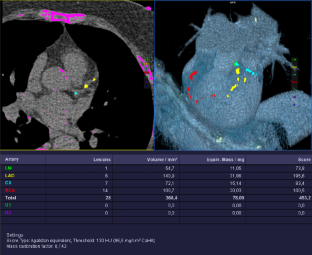

Fig. 3